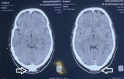

Case report: We have included five cases of osteochondromas occurring at rare locations with variable presentations and their management. We have included one case of metacarpal, one case of skull exostosis, two cases of scapula exostosis, and one case of fibula exostosis.